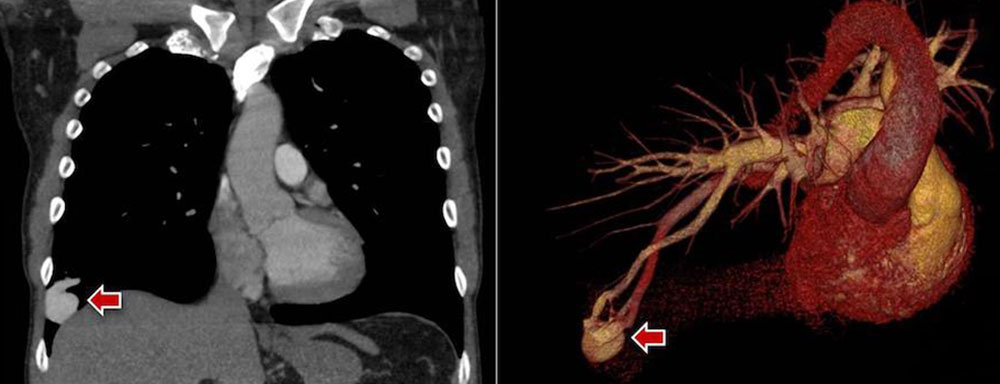

Arteriovenous fistulas: Pulmonary arteriovenous malformations in particular can be accurately imaged in a few seconds using the breath-holding technique after contrast enhancement.